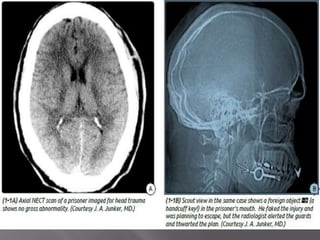

 Four components

1. Scout Image-

Look for cervical spine abnormalities such as fractures

or dislocations, jaw and/or facial trauma, and the

presence of foreign objects.